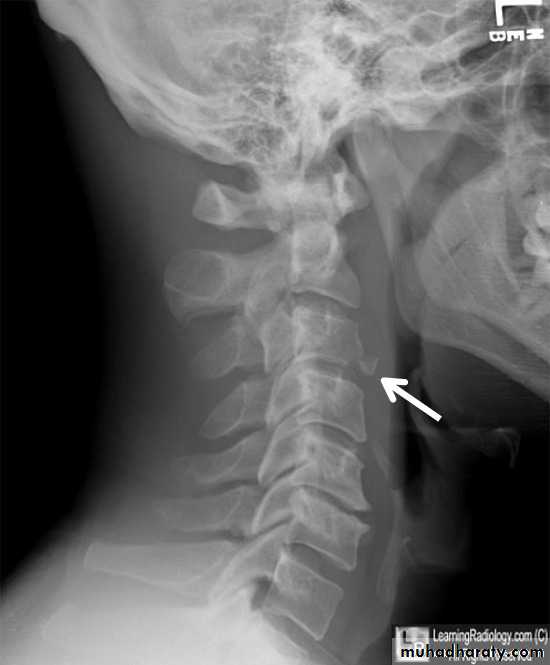

DIAGNOSISX RAY

Anterio posterior X ray radiograph.lateral radiographs with the head in flexion and extension may revealinstability that is not shown in the routine lateral film.

oblique views

at 45° are especially helpfula special projection

through the open mouth.Computed tomography (CT)

and magnetic resonance imaging (MRI).